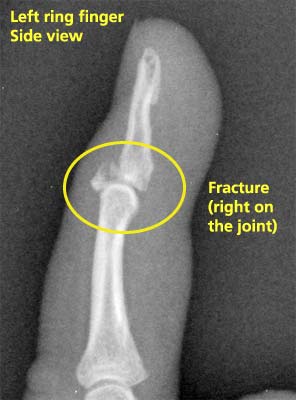

I made an instinctive grab for Jon as he fell, but missed. My left ring fingertip caught on his shirt as he went plop (very nicely on his bum, I might add. He’s always been surprisingly good at breaking his falls.) It was only a couple of minutes later that I noticed that my finger hurt. Over the evening it swelled up, went splotchy purple along one side, and still hurt. I guessed that it was a sprain and decided to splint it and wait to see how it felt, rather than cool my heels in emerg all night.

A day later the last joint of the finger looked puffy and purple, so with horrific visions of mallet finger dancing in my head I decided to go to the walk-in clinic and get it checked out.

Fast-forward two weeks and about 100 Advil later. I’m not sure the finger’s feeling worse, but it’s definitely not getting any better, so I get x-rays taken and go to my regular doctor.

x-ray of Laura's fractured fingertipX-rays come in the next day. Guess what! (Well, you’ve read the title, so you should know already.) Now I’ve exhausted the resources of family practice and have to haul my sorry finger to the orthopedic doctors at a hand clinic. However, apparently it’s extremely hard for a patient from a family doctor to get appointments at a hand clinic within a month (and by then your broken finger might be an orthopedic wreck). She was getting ready to call me to tell me to go to a hospital emergency room—that way I’d probably only have to wait a week to get to a clinic. Luckily the nurse doggedly called every hospital hand clinic she could think of until she lucked into an appointment for tomorrow morning (thank goodness for cancellations!)